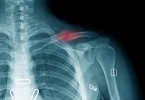

髋关节由髋臼和股骨头构成,髋臼为骨盆外侧的半球形凹陷,股骨头则是大腿骨顶端的球形结构。该关节被关节囊包裹,周围有髂股韧带、耻股韧带等多条韧带加固,内部存在盂唇结构以增加稳定性。从体表定位来看,髋关节大致位于腹股沟中点向大腿外侧延伸的区域,站立时髂前上棘与耻骨联合连线的中点可触及关节前侧。髋关节属于杵臼关节,具有屈伸、内收外展、旋转等多轴向运动功能,日常行走、跑步、下蹲等动作均依赖其活动。由于长期负重和活动磨损,中老年人易出现髋关节骨关节炎、股骨头坏死等病变,表现为腹股沟区疼痛和活动受限。